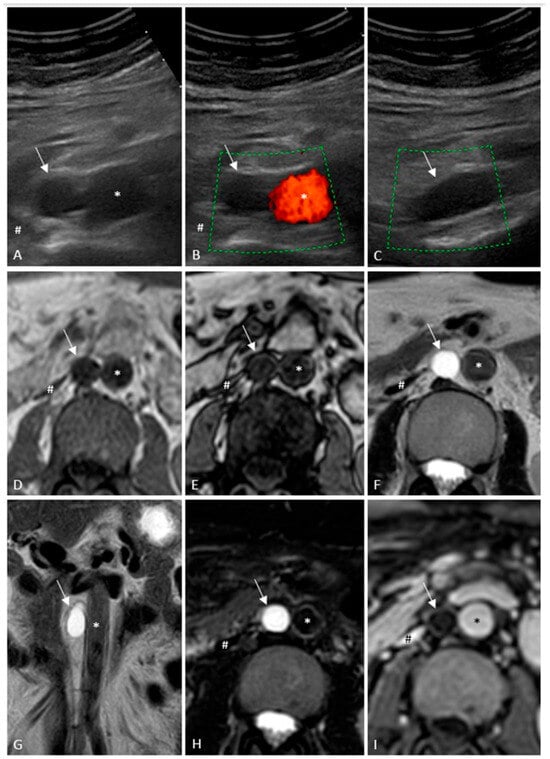

It is with great pleasure that I invite you to submit articles for the “Interesting images” Special Collection. Since we introduced Interesting Images as an article type in Diagnostics, it has served as a valuable resource for the imaging community. Many have relayed that they use these image-based case reports when encountering challenging cases or images of diseases rarely seen. Further, pitfalls are covered by this type of article and may be helpful both for experienced and less experienced image readers in making a correct evaluation.

The interesting Images together serve as a live imaging atlas covering PET, CT, MRI, and other imaging modalities. Therefore, the more cases we publish, the more likely it is that image interpreters with a difficult case can be supported by previously published cases. Although focus until now has largely been on clinical cases, it should be noted that nonclinical cases are also welcome, e.g., from preclinical in vivo imaging, including optical imaging as well as histology images from pathology.